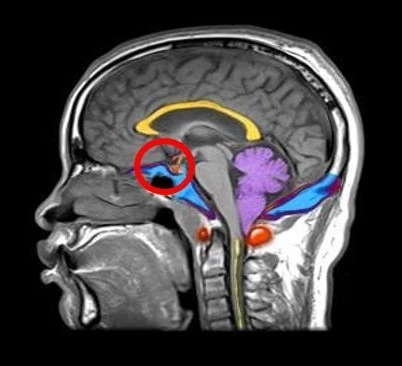

垂体是位于脑部正中央的⼀个器官(图1),它虽然体积小如黄豆,重不到1克,却控制着人体内其他所有内分泌腺体,是内分泌的司令部。